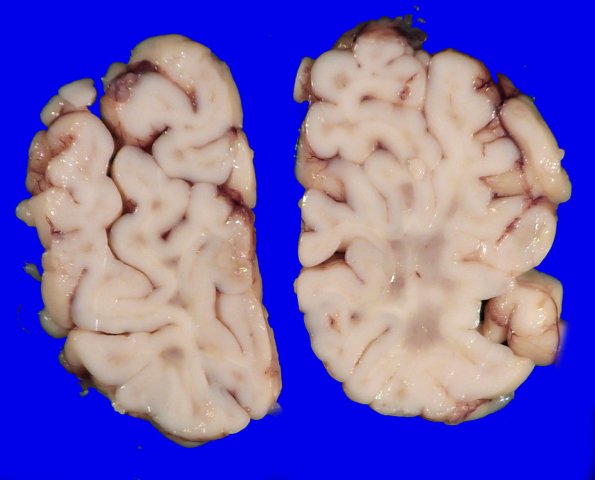

Washington University Experience | MISCELLANEOUS | Familial erythrophagic lymphohistiocytosis | 4A3 Lymphohistiocytosis (Case 4) Gross_2

4A3,4 The more caudal sections of parietal occipital lobe show more substantive white matter discoloration.